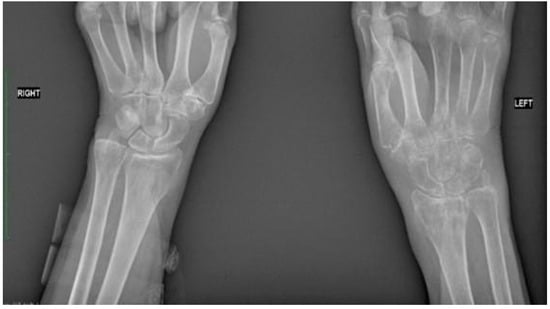

Figure 2.

Comparative radiographic assessment of two wrists in antero-posterior plain shows no bone pathology at the right site. Bone tissue rarefaction is clearly visible on the left side and appears to be like spots. It involves the left carpal bones, the left radial bone, and the proximal part of the I-V left metacarpal bones. There is a loss of joint space between carpal bones and between a distal row of carpal and metacarpal bones.